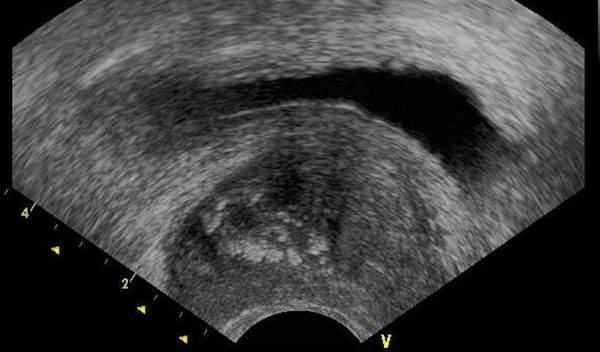

En la foto se muestra una ecografía de próstata, en la cual se aprecian cálculos intraprostáticos (círculos plomos). El paciente fue sometido a cirugía prostática.

Calficaciones intraprostáticas